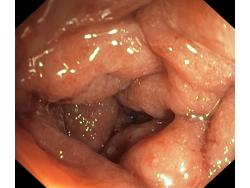

Zapalenie wrzodziejące jelita grubego